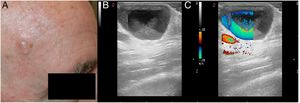

CASO 1: presentamos el caso de una mujer de 80 años con una pápula azulada de tiempo de evolución indeterminado, localizada en la mejilla izquierda (fig. 1). La lesión era asintomática. La ecografía mostró una lesión quística hipoecoica subdérmica con un Doppler color que demostraba un flujo turbulento (fig. 2). Se sospechó una ectasia venosa y se realizó una extirpación quirúrgica. El diagnóstico anatomopatológico final fue hidrocistoma.

Chin et al. evaluaron varios hidrocistomas empleando US. Sugirieron que dichas estructuras mostraban una lesión quística con una superficie hiperecoica y un centro hipoecoico (restos de lipofuscina) o un centro ecolúcido (líquido claro)3. Perez-Lopez et al. insistieron en la ausencia de flujo dentro de estas estructuras4. Sin embargo, en nuestros casos hemos visto que a veces estas estructuras pueden mostrar una señal Doppler positiva.

El pseudoflujo es un artefacto Doppler relacionado con el movimiento de otro líquido diferente a la sangre en ausencia de una estructura vascular, y se asemeja al flujo real de sangre en el Doppler color o en el power Doppler. La señal del Doppler color o del power Doppler aparecerá mientras se mantenga el movimiento del fluido. Sin embargo, si usamos el análisis espectral, este mostrará un patrón inconsistente con el flujo vascular2.

En nuestros casos, el movimiento del material en el interior del hidrocistoma condujo a una imagen en el Doppler color que puede interpretarse incorrectamente como flujo vascular.